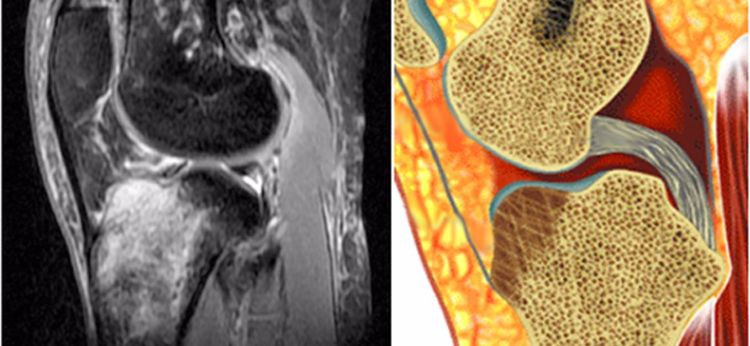

1.髓内水肿:主要是胫骨上段前方的骨水肿,就是平常所说的挡板征或仪表盘征。

如果站立位被撞击膝关节后上方则表现为股骨后髁水肿,不常见。

2.撕脱骨折:后交叉韧带胫骨附着点的撕脱骨折较常见。表现为胫骨平台后部有线形的T1加权低信号,T2加权,STIR高信号的骨折线,撕脱的碎片和后交叉韧带相连而韧带的连续性未见中断。